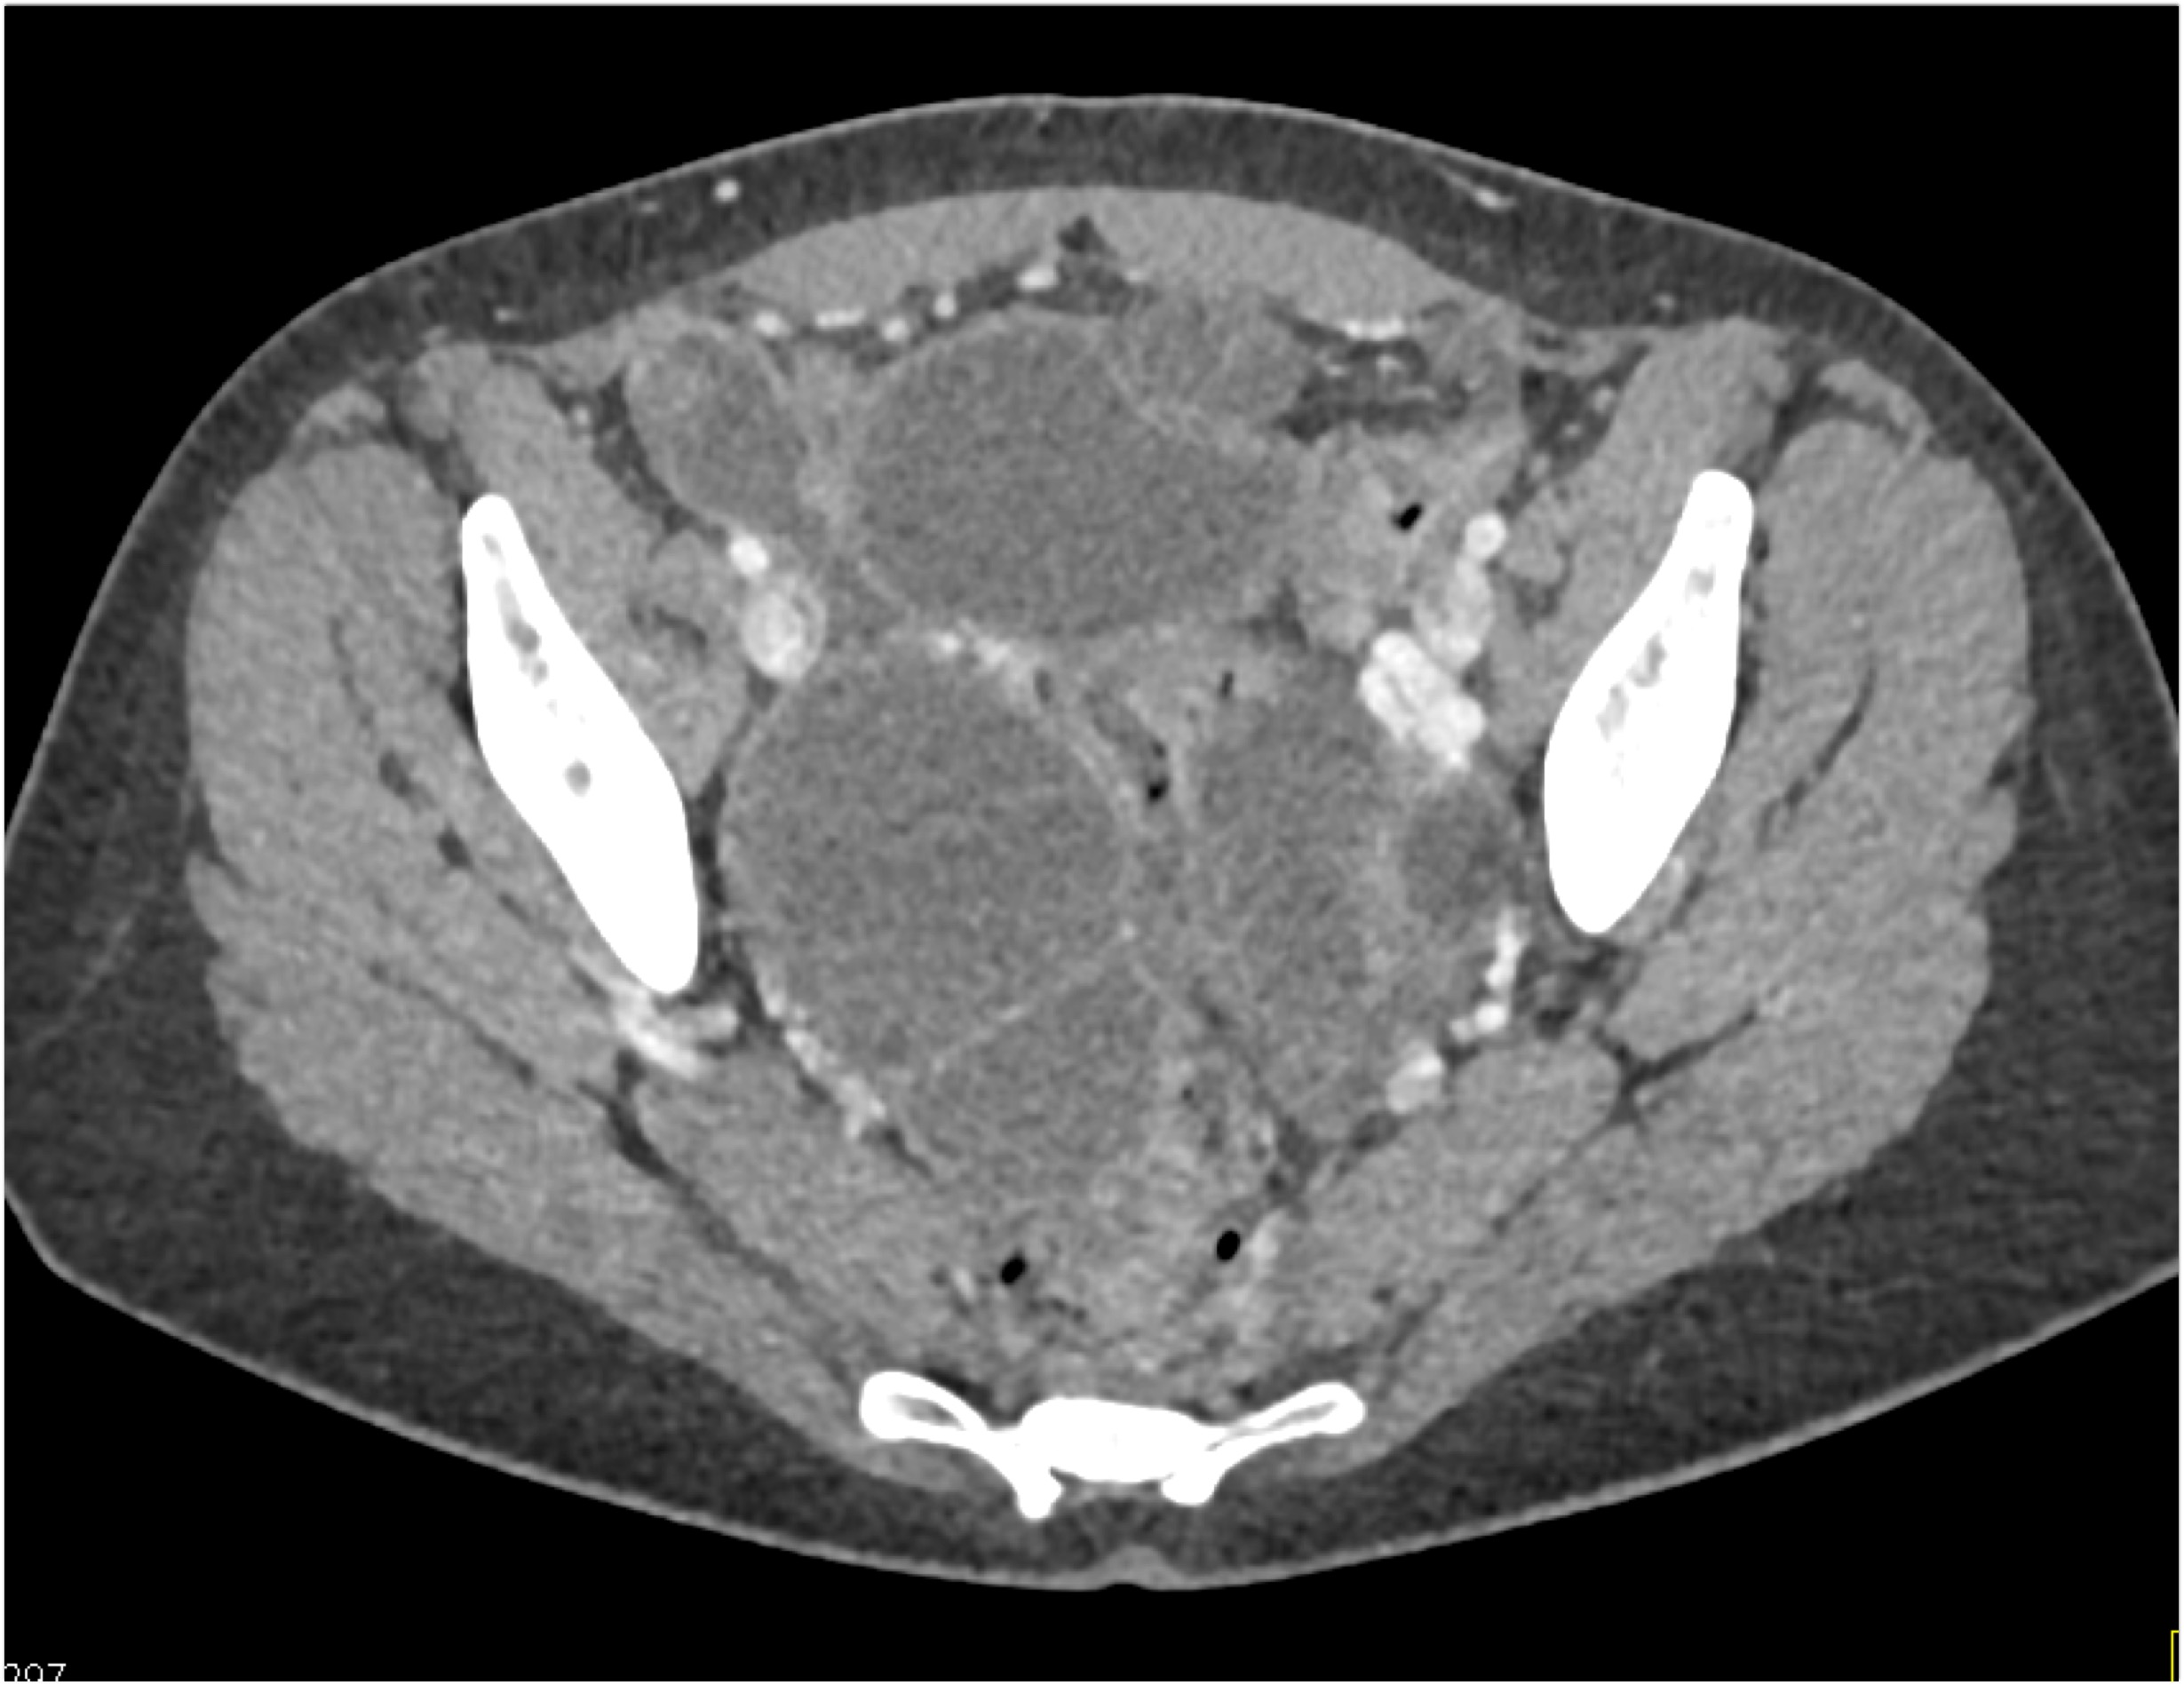

- Evaluate the CT images of each question carefully.

- Take time to make the call on the diagnosis for each individual question.